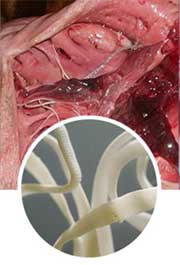

Parasites are multicellular protozoan organism, living at the expense of their host and make harm. Parasites first appear in intestines, then spread around the organism damaging all vital organs of a person:

Heart diseases, causing heart attack.